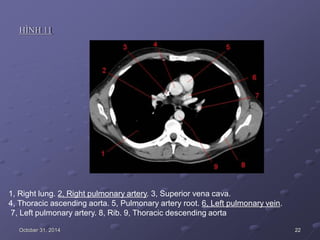

HÌNH 11

1, Right lung. 2, Right pulmonary artery. 3, Superior vena cava.

4, Thoracic ascending aorta. 5, Pulmonary artery root. 6, Left pulmonary vein.

7, Left pulmonary artery. 8, Rib. 9, Thoracic descending aorta

October 31, 2014 22